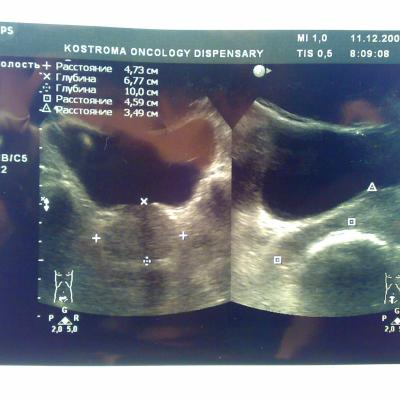

Посмотрите пожалуйста снимки узи, какие выводы можно сделать кроме увелечинных размеров? Может ли это влиять на эректильную функцию или изменение гормонального статуса? Болевых ощущений нет, есть небольшой дискомфорт, мочеиспускание в норме, но струя послабже чем была.Очень переживаю, ночами не сплю из-за нервов, без седативных уже и не уснуть.Заранее благодарен.

Ваши симтомы не связаны с предстательной железой. Вам нужен хороший психолог или психоаналитик. Уролог не нужен.